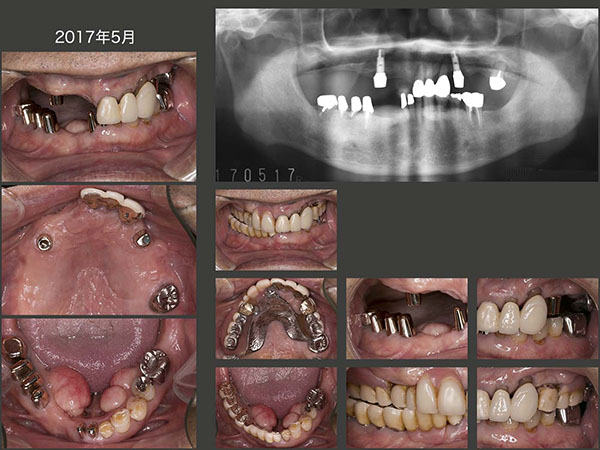

2014年8月,今回の治療が一区切りついた時の状態.この症例で片側処理の補綴を行う場合は,インプラントの助けが必要となる.植立位置は,上顎洞の前後とし,7mmおよび8.5mmの長さのインプラントを用いた.固定式のブリッジでも補綴処置は可能であるが,過去に可撤式の義歯を使用していた経験があること,また支台の清掃性を重視したいことから,コーヌス義歯を選択した.

しかし一つ大きな問題点がある.それは,インプラントをコーヌス義歯の支台とする場合,維持力が強くなり過ぎることである.コーヌス冠が天然歯の場合,咬合力が加わると歯根膜の弾性により,歯が若干圧下する.しかしインプラントは圧下しないために,外冠が必要以上に内冠に食い込んでしまう.外冠咬合面の内面に箔を貼り,外冠が変形して食い込むのを防ぐようにしても,インプラントの場合は,箔が咬合力により直ぐに潰れてしまう.これは避けられない問題であるが,この患者さんは着脱機を用いて,義歯を外してもらっている.(もちろん,最初から説明,納得してもらっている.)

上顎の歯槽骨はほぼ海綿骨で,インプラントを支えるにはあまり適していないことから,今後の経過を注意深く観察する必要がある.(20年11月現在,特に問題なく経過している.)